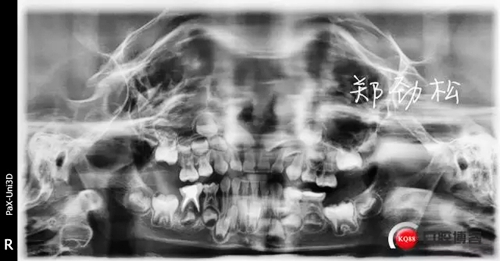

我的病例三 7E牙髓炎

836605.jpg

297418.jpg